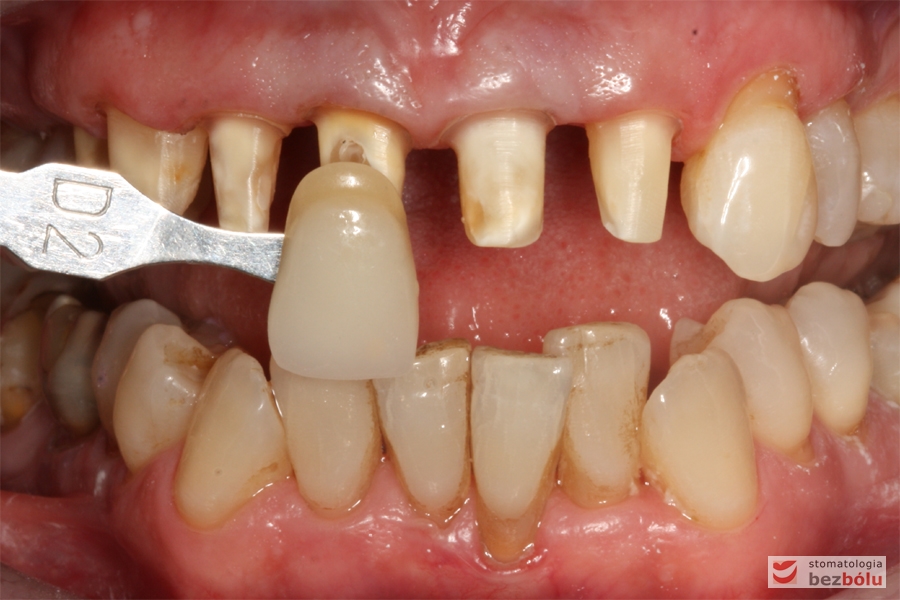

Dobór koloru dla nowych zębów - dobór koloru w odniesieniu do górnego kła po lewej stronie

Dobór koloru dla nowych zębów – dobór koloru w odniesieniu do górnego kła po lewej stronie